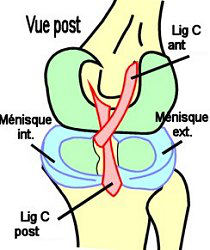

Moyens d'Union Passifs

-

la

capsule, qui est renforcée à l'ARR pour former les 2 coques

condyliennes, est tapissée sur sa face interne d'une synoviale. En AV

elle contient la patella,

- le ligament croisé antérieur (ou antéro-externe) est tendu de

l'aire intercondylaire ant. à la face interne du condyle latéral, il

est renforcé par la corne antérieure du ménisque externe. Le ligament

croisé postéro-interne est tendu de l'aire intercondylaire post. à la

face externe du condyle médial. Les ligaments

croisés sont situés dans la fosse intercondylaire (old.

échancrure intercondylienne), ils sont intra-capsulaire mais

extra-synoviale. Ils limitent les mouvements de torsion.

Les ligaments croisés (lig. C) antérieur et postérieur sont croisés

dans :

- le plan sagittal (ligament ant. : presque horizontal, ligament

post : presque vertical) et

- le plan horizontal (ligament ant. : oblique de DD à DH, ligament

post. : oblique de DH à DD).

-

Les ligaments collatéraux tibial (1) et fibulaire (2) (old.

LLI et LLE) :

- Le ligament collatéral médial (ou tibial) est tendu en ARR et DD

du condyle médial du fémur à la partie supérieure de la face

interne du tibia (avec des fibres superficielles fémoro-tibiales

et des fibres profondes qui disparaissent dans le ménisque médial

et le renforcent)

- Le ligament collatéral latéral (ou fibulaire) est tendu de l'ARR

et DH du condyle latéral à la face supérieure de la tête de la

fibula.